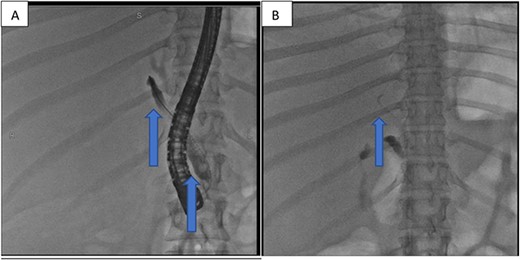

At our facility, ERCP was done. The bile duct was cannulated with 0.035 wire-guided sphincterotome. Cholangiogram showed normal caliber biliary tree with one filling defect in the distal CBD and contrast leak from duct of Luschka to the gall bladder bed (Fig. 1). There was no contrast leak from the cystic duct stump (Fig. 2A). Standard sphincterotomy was performed and a single mulberry stone was removed using stone retreival balloon and double pig tail biliary plastic stent was placed into the RHD and good bile flow was achieved post procedure (Fig. 2B).

(A) First fluoroscopic image shows evidence of no bile leak from cystic duct stump as indicated by the arrows; (B) second fluoroscopic image shows a stent placed into the RHD.